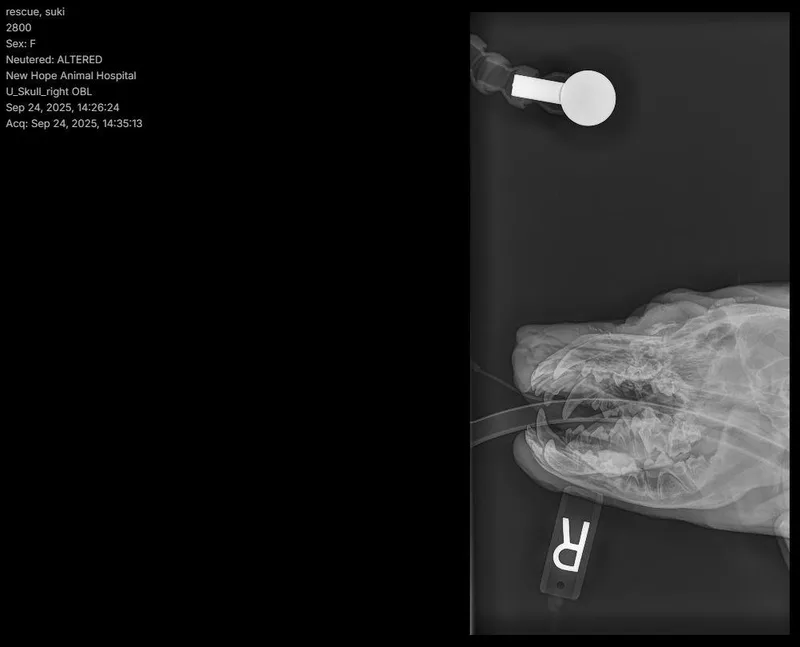

Suki has reached a wonderful milestone — she's feeling good, healing beautifully, and ready to find her forever home. After thorough veterinary care, it was discovered that Suki had suffered past head trauma that caused swelling, infection, and discomfort. Once a hidden bone fragment was removed, her body began to heal almost immediately — and the change has been remarkable. Today, Suki is brighter, more comfortable, happier, more playful, and clearly feeling like herself again. While she still has follow-up care and possible specialty treatment ahead, she's in a stable place and ready to move forward into a loving home where she can continue healing surrounded by care and consistency. Suki is a gentle, resilient girl with a calm spirit and a sweet heart. She's handled everything thrown her way with grace and trust, and she's ready for a new chapter filled with safety and love. **Suki is being fostered in Austin, TX. Paid transport can be arranged. Transport costs range from $200-400.** If you are interested in adopting, please complete an application @ https://form.jotform.us/41173109602142. Once approved, home visit and reference checks are also required. If you have further questions outside of this listing, please email chowmail.hccc@gmail.com.